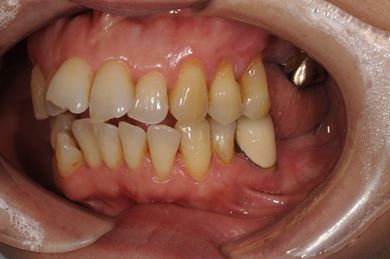

インプラントの症例写真 IMPLANT

インプラント治療+ソケットリフト+GBR

| 性別/年齢 | 女性 / 55歳 | ||||||||||||||||||||||||||||||||

| 主訴 | 奥歯が3本抜歯されてしまったあとにインプラントを入れたい。 | ||||||||||||||||||||||||||||||||

| 治療内容 | インプラント3本(ソケットリフト、GBR)、ハイブリッドセラミック3本 | ||||||||||||||||||||||||||||||||

| 総治療費 | 1,295,300円 | ||||||||||||||||||||||||||||||||

| 治療期間 | 8ヶ月 |